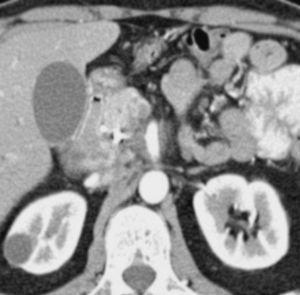

A partir de la complementación de la US con técnica de doppler color ha mejorado el rendimiento de la misma en la evaluación de la extensión tumoral a los vasos arteriales y venosos peripancreáticos, que oscila entre el 84 y el 87%3,4 (fig. 1). Tomiyama et al5 evaluaron la extensión vascular arterial tumoral en 33 pacientes mediante US doppler color, comparando sus hallazgos con los de la angiografía, la cirugía y la pieza de resección. En los 11 pacientes intervenidos describen una sensibilidad del 60%, especificidad del 93% y rendimiento diagnóstico del 87%. En la evaluación conjunta de todos los pacientes incluidos en el estudio concluyen que la US doppler color ofrece un rendimiento diagnóstico superior al de la tomografía computarizada (TC) (72%) y similar al de la angiografía (91%). No obstante, el escaso número de pacientes con correlación patológica supone, en cierto modo, una limitación a las conclusiones de los autores. Hasta donde hemos podido revisar Minnitti et al6 presentan los mejores resultados publicados por el momento, detectando el adenocarcinoma pancreático mediante US en 61 de los 64 pacientes incluidos en su estudio (95,3%), y obteniendo mejores resultados que la TC helicoidal, cuyo índice de identificación tumoral fue del 89,1%. El tamaño promedio de los tumores detectados en la US fue de 3,2 cm (rango: 1,5-6,8 cm), aunque los autores no presentan la correlación patológica del tamaño tumoral medido en la pieza quirúrgica en los 18 casos en los que se pudo llevar a cabo la resección radical del tumor. Los autores presentan un índice de predicción de resecabilidad del 81,4% para la US, algo inferior al obtenido por la TC (86,0%), calculado sobre los 43 pacientes laparotomizados de la serie. Sin embargo, estos buenos resultados no han sido refrendados en la literatura por otros autores hasta el momento.

Fig. 1.--Ecografía abdominal. (A) masa hipoecoica de 8 4, 5 cm en la cola del páncreas, en íntimo contacto con la vena esplénica (2). (B) Estudio doppler color y pulsado que demuestra la permeabilidad de la vena esplénica con un registro sin alteraciones.